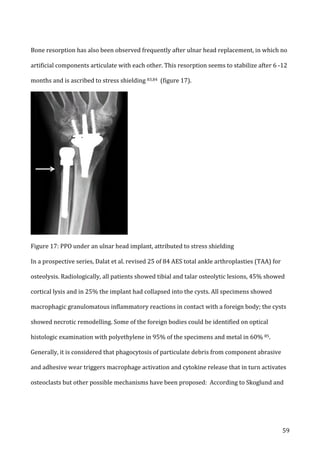

1-­‐3

years

(figure

8a

and

b).

In

a

small

percentage